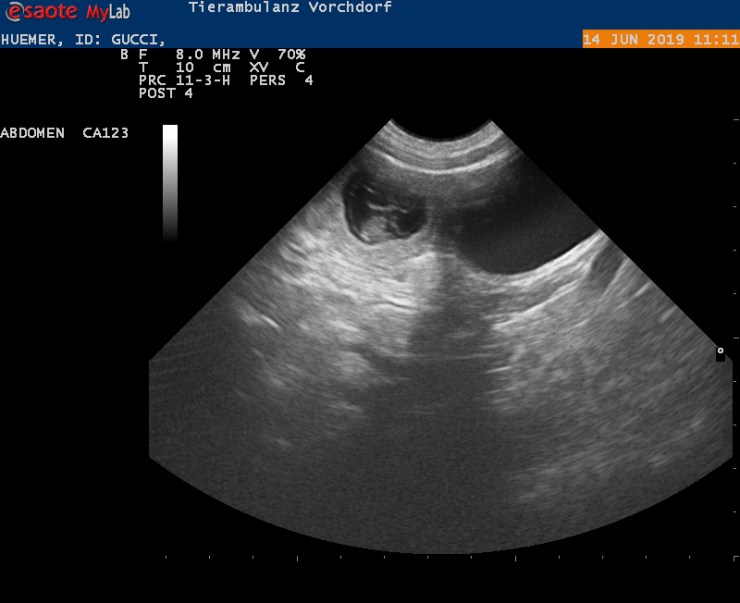

Ich freue mich jetzt auch bekanntgeben zu dürfen, dass der voraussichtliche Geburtstermin der 20. / 21. Juli sein wird.